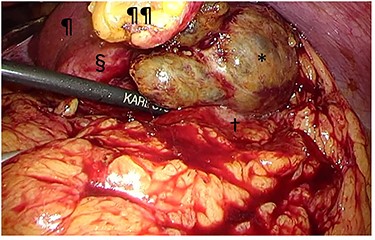

Intraoperative findings. The tumor (§) with its protruding content (*) was adherent to the greater omentum and stomach (†). The tumor was bluntly dissected and no peritoneal dissemination was observed. ¶liver; ¶¶divided round ligament.